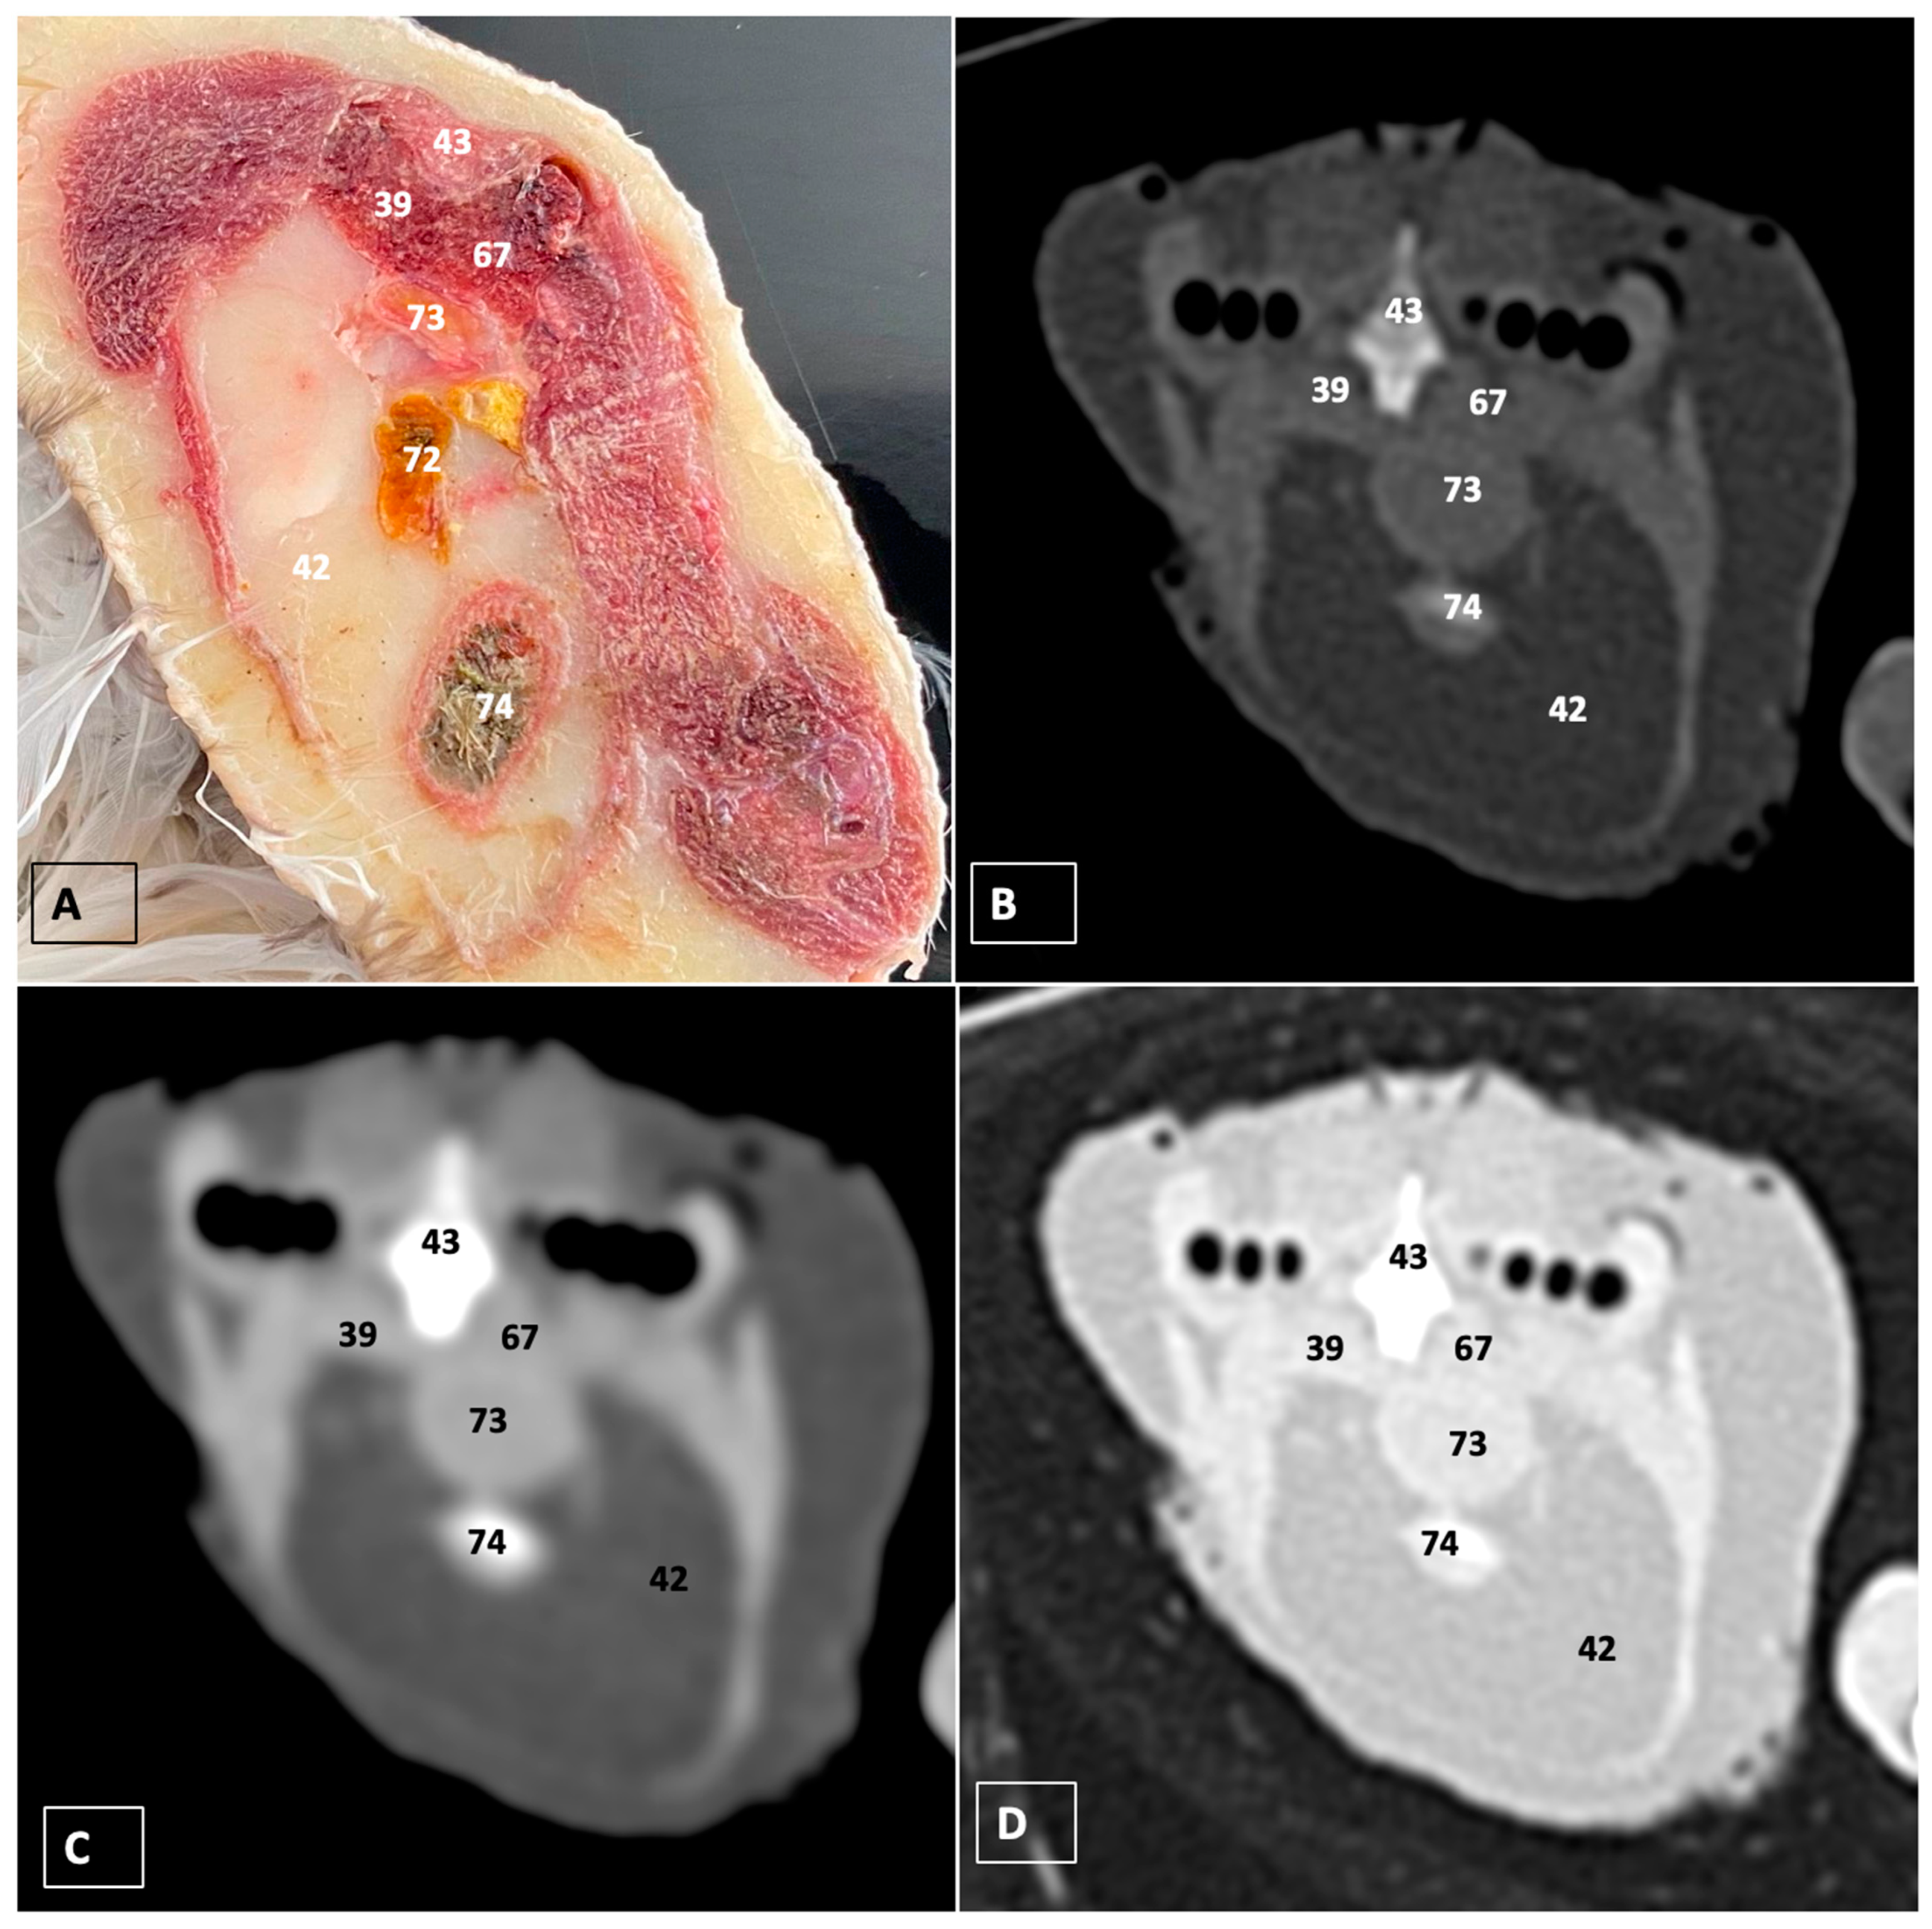

3. Results

3.1. Anatomical Dissections and Cross-Sections

3.2. Computed Tomography Images